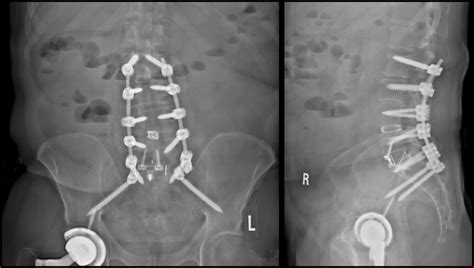

The vertebrae are stabilized using screws, rods, or plates. The incision is then closed in layers, and the patient is taken to the recovery room.